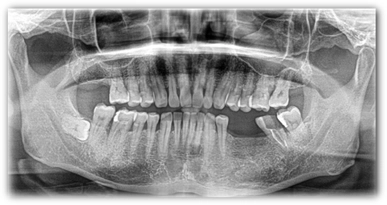

植牙案例分享:

C先生左下缺兩顆牙齒加上第二大臼齒因蛀牙剩下殘根,讓他長期習慣用右邊進食,這樣也使臉部肌肉不對稱,俗稱 [ 大小臉 ] ,嚴重可能臉部歪斜,外觀受到影響。

透過醫師幫病患做骨質再生手術以及植牙重建,讓患者能夠恢復原本的咀嚼功能。

人工植牙

治療前

治療後

▲ 本影像僅供醫療說明參考,療效因個人狀況不同,應由專業醫師評估